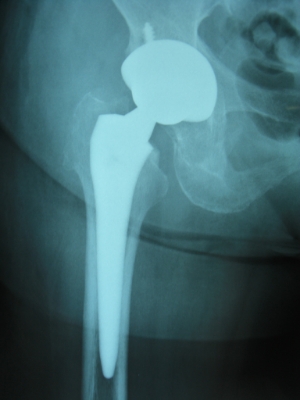

リウマチ性股関節症のレントゲン像

THA術後

リウマチ性股関節症と急速破壊型股関節症

いずれの疾患も変形性股関節症によく似た経過を辿り、しかも比較的早期に関節そのものが破壊されますので人工股関節置換術が主として行われています。 骨盤側に突出した場合には骨移植とサポートリングといった補強材料を用いた再建術を行っています。ステロイド治療などにより極度に骨粗鬆症が進行した患者さんにおいては、 セメント人工股関節の使用および院内骨銀行の保存骨を用いた骨移植手術も併用することが可能です。 当科では生物学的製剤治療を実施されている患者様におきましても安全に手術療法が受けられるよう、 十分な周術期管理がなされておりますので安心して治療を受けていただくことが可能です。